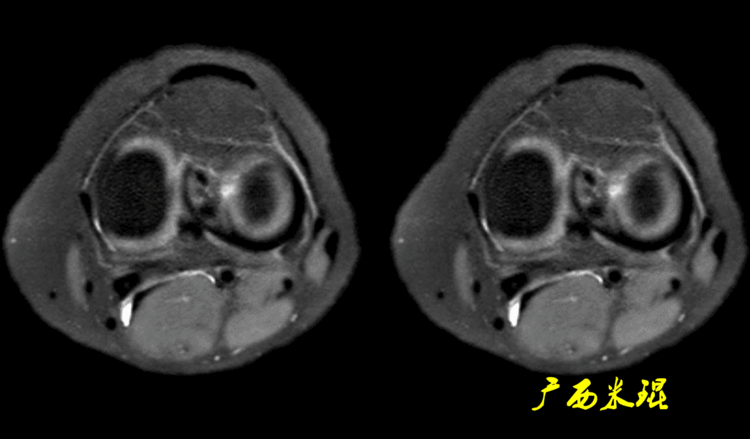

膝下内侧动脉、膝下外侧动脉等共同组成血管环,MR轴位上也常常被误诊为半月板关节囊分离,其实两者完全不同。